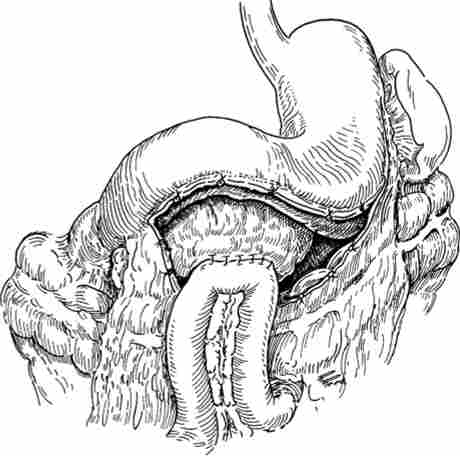

З метою ліквідації кіст, порожнину яких підтримувалася завдяки повідомленню її з протоковой системою ПЖ, застосовується так зване внутрішнє дренування кіст шляхом анастомозірованія їх з просвітом шлунка, дванадцятипалої або тонкої кишки (цістогастростомія, цістодуоденостомія, цістоеюностомія з вимкненим з травлення ділянкою тонкої кишки (рис. 20.19 )).

накладення цістоеюноанастомоза

Мал. 20.19. накладення цістоеюноанастомоза

Однак останнім часом ці втручання здійснюються все рідше, оскільки патологічне сполучення між протокою ПЖ і псевдокісти буває вузьким, може періодично закриватися і не забезпечувати ліквідації протоковой гіпертензії, характерною для хронічного панкреатиту. Крім того, при цістогастро- і цістодуоденостоміі можливий закид в кісту шлункового вмісту, що підтримує інфікованість порожнини і перешкоджає її облітерації.

Тому основним сучасним методом лікування псевдокист виступає їх зовнішнє дренування з наступним накладенням широкого ПЕА з виключеною по Ру кишкової петлею (операція Пьюстау-П) при наявності протоковой панкреатичної гіпертензії.